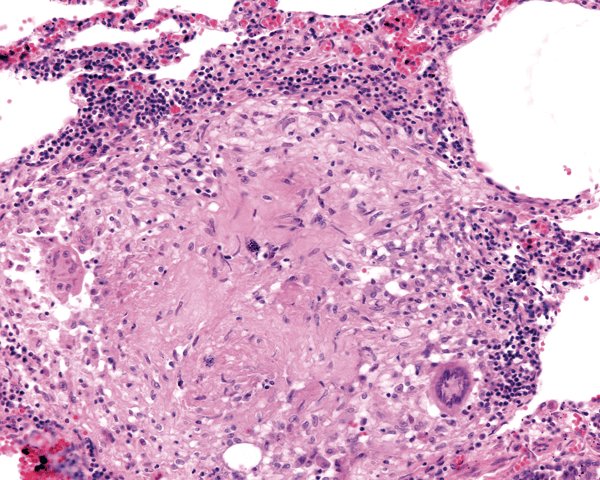

Entre los OLTs sobresalen los granulomas, estructuras similares a un ganglio linfático, con acúmulo de macrófagos y células gigantes multinucleadas de 40 a 60 micras de diámetro, con 15 o más núcleos. No se sabe si estas se forman por división incompleta de un macrófago o por fusión de varios de ellos. Estas células gigantes están rodeadas de linfocitos, especialmente CD4 y CD8. En el interior del granuloma hay formación de nuevos capilares con epitelio cuboide, que permite el ingreso de las diferentes células que conforman el granuloma (Figura 4).

Figura 4. Aspecto y arquitectura de un granuloma.